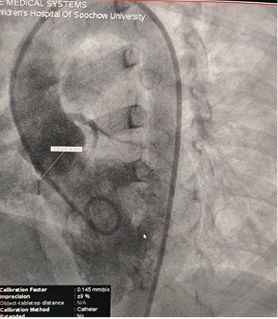

Resultados pré-operatórios do eco:

Diâmetro base: ~ 6.1mm com saída múltipla pontos

Tecido semelhante a membrana observado sobre o defeito

Doppler colorido: fluxo de derivação da esquerda para a direita

Diagnóstico: VSD perimembranoso

Selected MemoSorb ABFDQ-II 9 occluder based on intraoperative angiography and echocardiographic assessment.